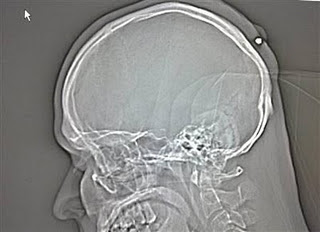

2. Peluru 5 tahun dalam kepala

Seorang pria yang hidup di Jerman hidup dengan normal dan baik-baik saja selama lima tahun tanpa menyadari ia telah ditembak di kepala. Peluru kaliber 0,22 ditemukan ketika orang itu pergi ke dokter untuk memiliki apa yang ia pikir merupakan kista . Yang dia ingat adalah bahwa ia telah menerima pukulan ke kepala sekitar tengah malam di sebuah pesta Tahun Baru tahun 2004 tapi sudah lupa tentang hal itu karena ia “sangat mabuk.”